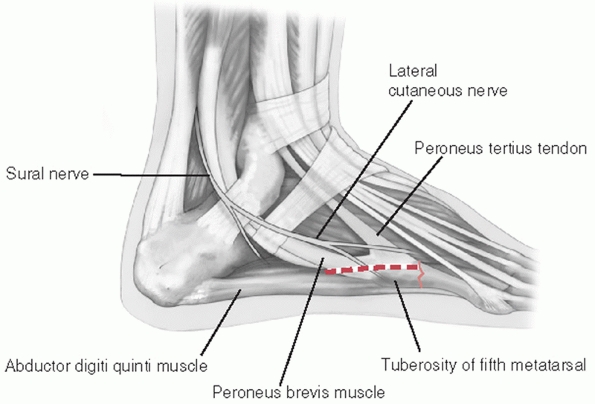

strength of individual ligaments across many of these joints. The

important characteristics to note are (a) the plantar ligaments are

significantly stronger than the dorsal ligaments, (b) the multiple

ligaments overlap among the joints of the lesser four tarsometatarsal

joints, and (c) the Lisfranc ligament, which is the largest and

strongest ligament of this joint complex, represents the only

ligamentous support between the medial leg and the middle and lateral

legs in the forefoot. The Lisfranc ligament originates from the plantar

lateral aspect of the medial cuneiform just below the plantar extent of

the second tarsometatarsal joint and inserts on the plantar and medial

aspect of the second metatarsal base. At best it is an indirect link

between the first and second metatarsals. There is no interligamentous

connection between the first and second metatarsal.

are important for management are stability and associated fracture

management. Extra-articular fractures, which appear with these

injuries, should be treated as described elsewhere in this text to

preserve that structure’s role in foot function. Intra-articular

fractures of the tarsometatarsal joints should be handled in the

context of the treatment of the joint complex.

with metatarsal motion, and tenderness to palpation but fail to exhibit

any instability should be considered a sprain. In addition to the

normal concept of rest, ice, compression, and elevation (RICE) for

treating sprains, the need for immobilization is important. These

injuries can be severely debilitating and require a long recovery

period.24,76

Nondisplaced ligamentous injuries with or without small plantar

avulsion fractures of the metatarsal or tarsal bones should be placed

in a well-molded short-leg walking cast (Table 60-5).

Initially, the patient is kept non-weight bearing with crutches and

only permitted to bear weight as comfort allows. Once full weight

bearing can be accomplished in a cast, the patient is tested for